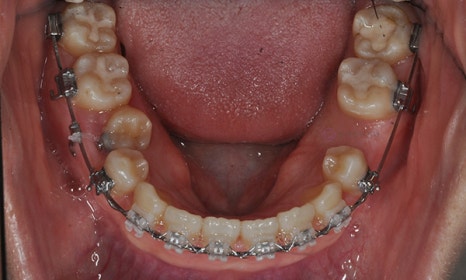

본 환자분은 오른쪽 아래 유구치(유치 어금니)가 남아있고 그 안쪽에 두번째 작은 어금니가 나와 있었습니다. 나머지 세 부위의 두번째 작은 어금니들은 영구치 치배가 없어 유치 어금니로 사용해온 상태였습니다. 왼쪽 아래는 뿌리만 남아있었고, 오른쪽 위에는 유치 어금니가 빠지고 공간이 비어 있었으며, 다행히 왼쪽 위 유치 어금니는 아직 남아 있는 상태였습니다. 아래는 오른쪽의 유치 어금니 및 왼쪽의 비어 있는 어금니 공간이 많이 남아 있고, 상대적으로 위에는 어금니 공간이 부족하여 위아래 앞니도 제대로 물리지 않고 있었습니다.

오른쪽 아래 치아들과 같이 치아가 겹쳐져 있게 되면, 교합이 맞지 않을 뿐만 아니라 그 사이 부위의 구강위생관리가 제대로 이루어질 수 없기 때문에 충치가 생길 확률이 높으며, 잇몸도 안좋아질 수 있습니다.

오른쪽 아래 작은 어금니에 버튼을 붙여 고무줄을 걸어 제위치로 끌어당기고 있는 모습입니다.